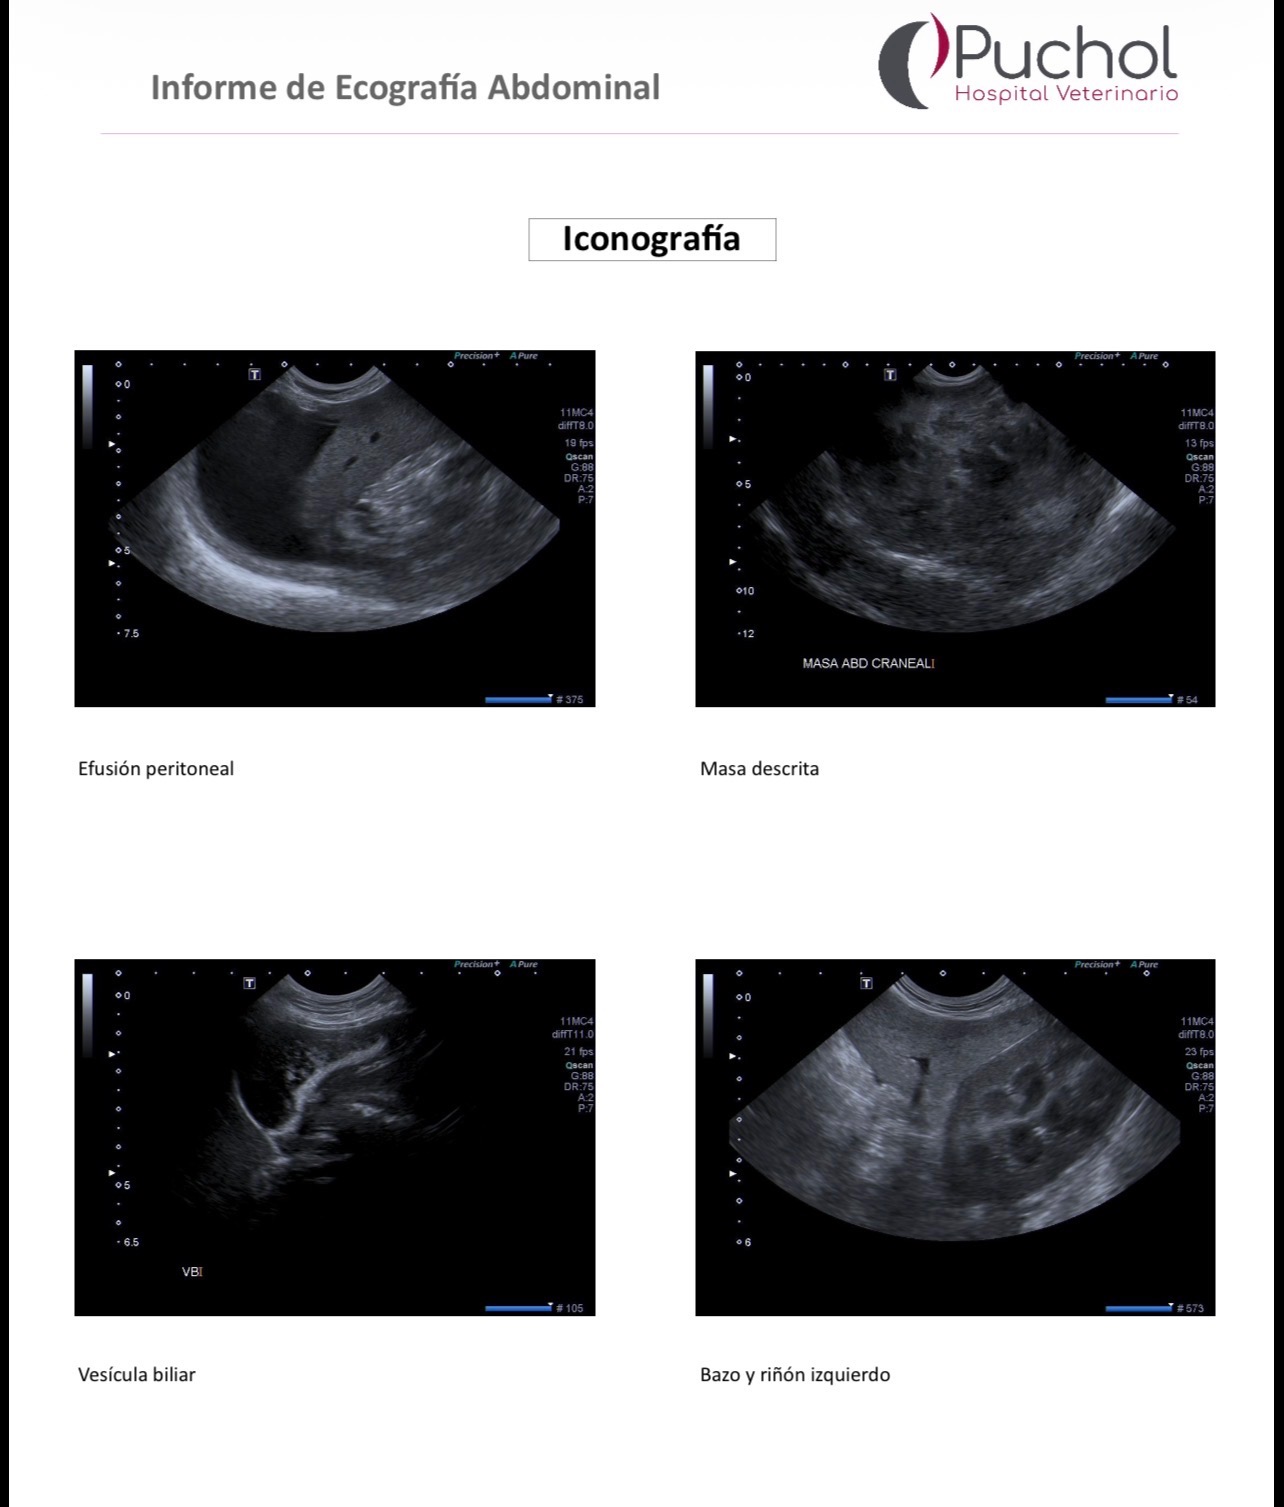

Hace unos días comenzó a encontrarse mal y, tras varias pruebas en el hospital veterinario, los médicos han encontrado una gran masa de más de 12 cm en su abdomen, situada entre el hígado, el estómago y el bazo.

Esta masa está provocando una hemorragia interna (hemoabdomen) y requiere una cirugía urgente y compleja para poder extraerla.

Es una operación delicada porque la masa está en contacto con el hígado, y los veterinarios necesitan intervenir cuanto antes para detener el sangrado y darle una oportunidad.